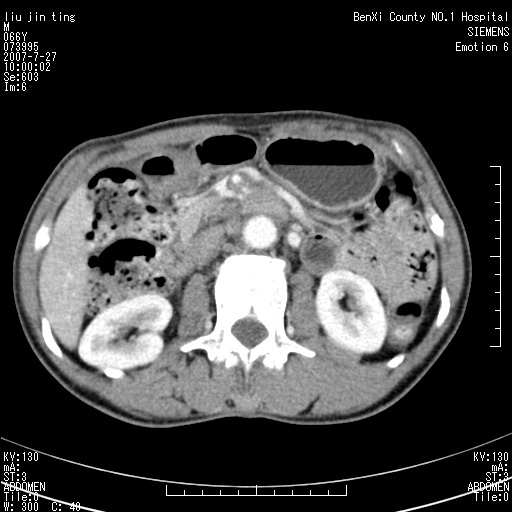

腹痛,背痛,无恶心呕吐,不黄,彩超示胰腺钩癌,ct扫描病灶平扫30-40hu,增强后动脉期40--60hu,静脉期50-68hu,真的是钩突上的么?您要试一试么?

腹腔干至肠系膜上动脉水平肿大淋巴结影可能性大.

腹腔干至肠系膜上动脉水平肿大淋巴结影

钩突是正常的,只见腹膜后淋巴结的肿大,考虑淋巴瘤或转移可能。

腹膜后占位性病变,首先考虑肿大淋巴结。

后腹膜肿块,包围血管,考虑淋巴恶性病变,淋巴瘤或转移。